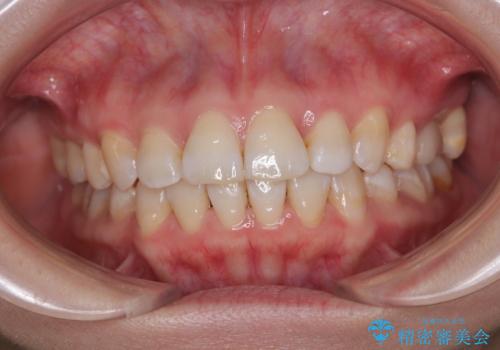

[セラミック治療] 前歯の審美治療に伴う矯正治療